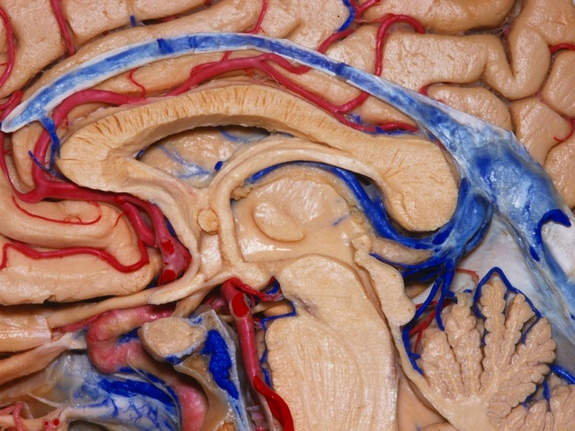

Aquí, el hemisferio izquierdo se ha eliminado casi por completo, dejando al descubierto la superficie de la parte derecha del cerebro una vista medial. Se puede ver como las arterias y venas serpentean a través del tejido cerebral. La gran estructura blanca, en forma de cuerno en el centro es el ventrículo lateral que forma parte del sistema ventricular por el que circula el líquido cefalorraquídeo.

Aquí, el hemisferio izquierdo se ha eliminado casi por completo, dejando al descubierto la superficie de la parte derecha del cerebro una vista medial. Se puede ver como las arterias y venas serpentean a través del tejido cerebral. La gran estructura blanca, en forma de cuerno en el centro es el ventrículo lateral que forma parte del sistema ventricular por el que circula el líquido cefalorraquídeo.

En este caso, el cerebro ha sido cuidadosamente cortado a la mitad, una “sección sagital media.” En esta imagen destaca la glándula hipófisis, la pequeña pieza redonda rodeada de vasos sanguíneos, que se encuentra justo detrás de la nariz y por debajo de una región del cerebro llamada hipotálamo (parte inferior izquierda). Llamada la “glándula maestra”, la hipófisis libera hormonas que influyen en otras glándulas.